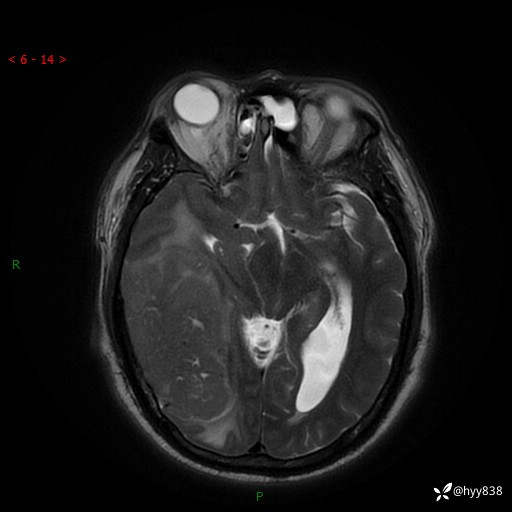

患者性别:男

患者年龄:56岁

简要病史:外院CT提示脑膜瘤,为进一步诊治来我院

辅助检查:MRI

临床诊断:颅脑占位

颅脑MRI平扫+增强